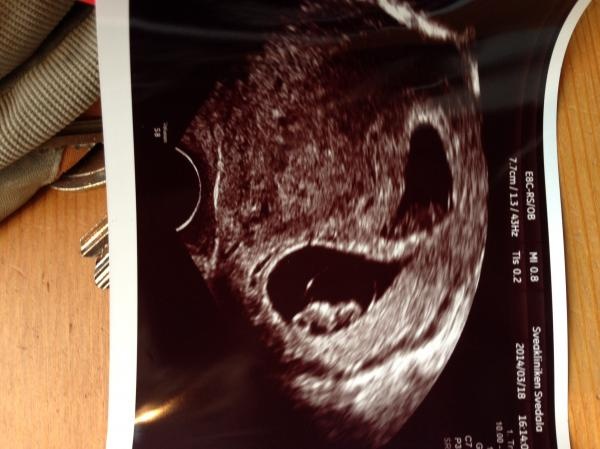

En tråd för oss som har BF i Oktober 2014. Här kan vi samlas och prata om allt möjligt. Plussade idag 20 januari och har enligt FL graviduträknare BF 2 oktober. Bor i Skåne och har en dotter som föddes 29 september 2011.